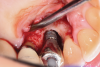

A surgical approach was planned that included implantoplasty and guided bone regeneration. After local anesthesia was administered, full-thickness flaps were elevated using an envelope flap on the buccal aspect and a triangular design on the palate to expose the defects. Removal of granulomatous tissue from the area enabled visualization of a narrow circumferential lesion on the facial (Figure 3) and a one- to two-wall combination defect on the palatal (Figure 4). The surface was initially treated with a 50% solution of citric acid for 30 seconds followed by thorough rinsing with sterile saline. This was followed by implantoplasty using a 30-fluted finishing bur of surgical length. Because the implant was very narrow, achieving a matte-like surface was not possible; thus, the goal was to reduce the threads and lightly remove the implant's outer surface to expose fresh titanium (Figure 5 and Figure 6). The modified surface was treated again with citric acid and rinsed with sterile saline.

Fig 3. A narrow three-wall infrabony defect was visualized on the facial of the implant.

Figure 3